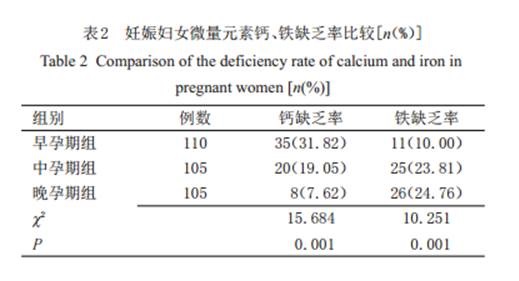

《当代医学》320名孕妇数据:妊娠过程易出现钙铁缺乏

2020年10月,国家级期刊《当代医学》刊发了《孕期微量元素钙铁值测定结果临床分析》,分析结果是基于九江市妇幼保健院妇产科自2018年1 月至2019年2月,抽样320名孕妇,针对孕期微量元素水平进行研究调查的数据。结果显示:妊娠过程中孕妇易出现钙铁缺乏,因此需在妊娠早期加强钙元素的补充,在妊娠中期加强铁元素补充。

钙是构成胎儿骨骼和牙齿的主要成分,还具有维持肌肉心脏与神经兴奋性的生理作用,在妊娠时期,孕妇发生手足抽搐、腰腿酸痛等问题是由钙的摄入量不充足引起的。有研究表明,缺钙可引起血压升高,导致妊娠高血压,补充钙剂减轻钙缺乏的症状,能够降低孕妇的血压,从而降低妊娠期高血压病的发生率。

有资料报道,孕妇贫血原因中铁缺乏所致贫血占81%,当母体内铁元素缺失严重时,会导致胎儿体内出现铁缺失,由此引发新生儿贫血的出现。新生贫血会导致其对机体抵抗力产生不利影响,使新生儿出现感染、生长发育等迟缓情况,使围产儿死亡率提高。